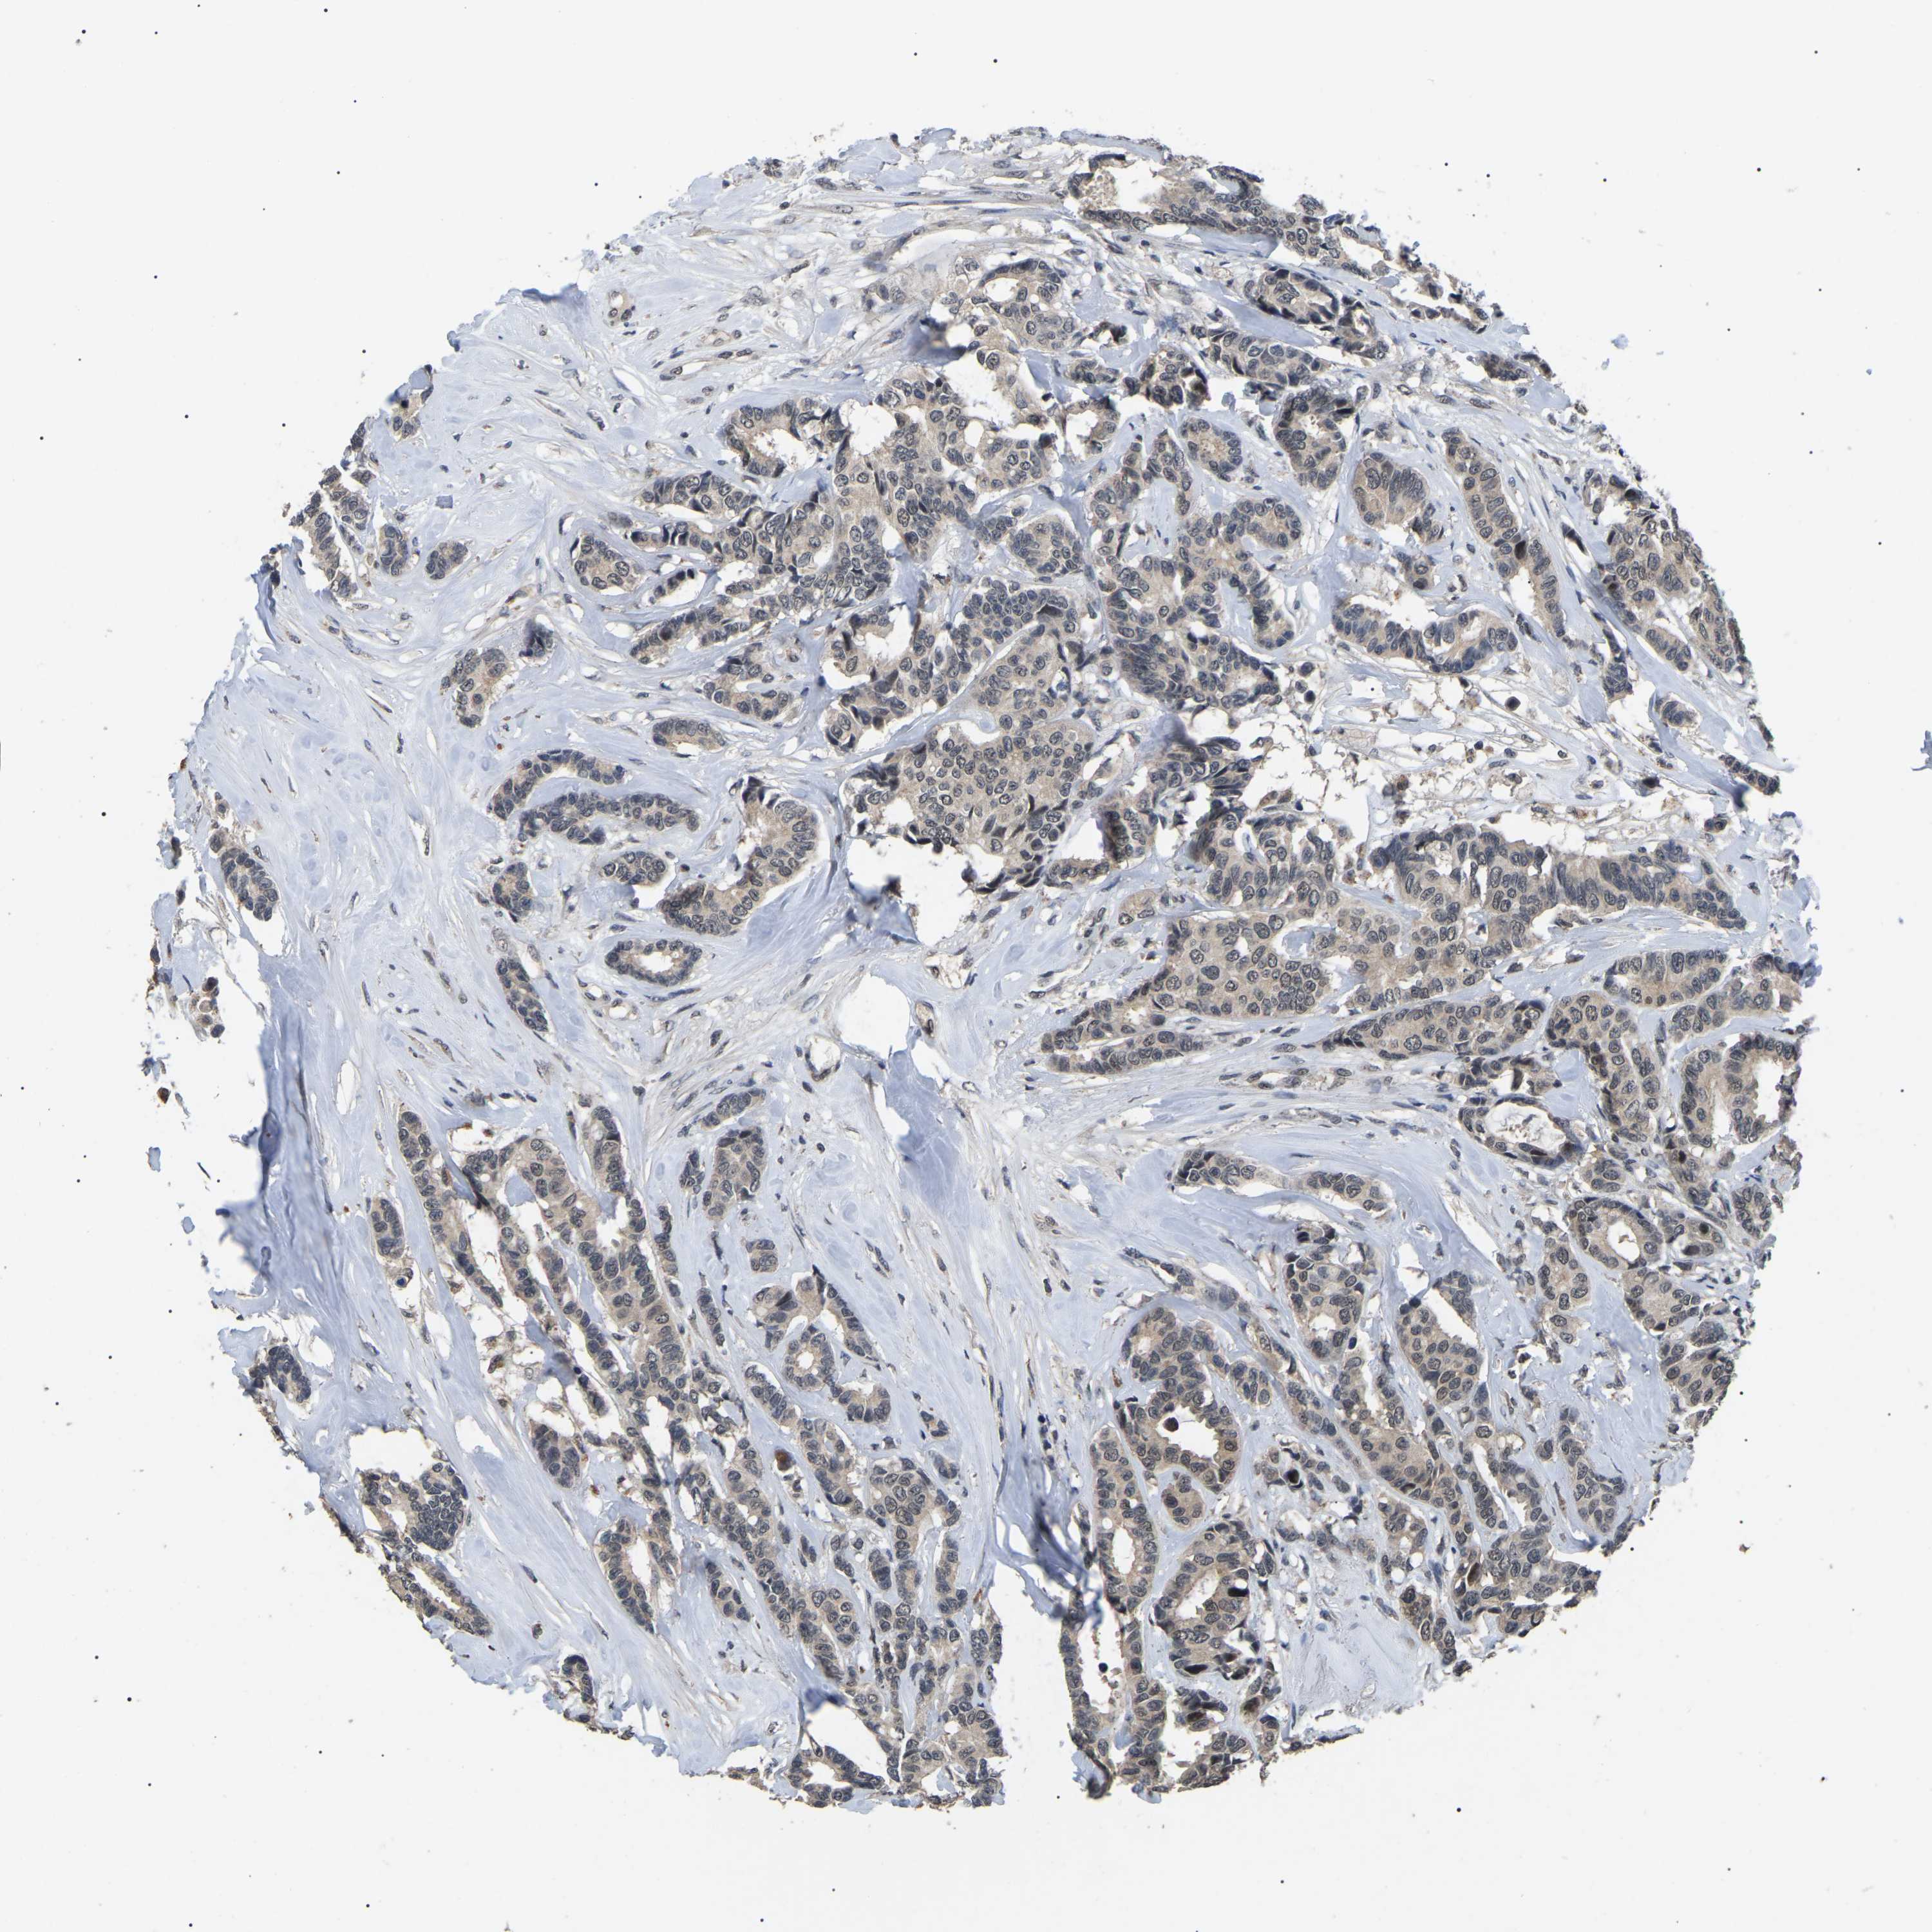

CANCER BREAST CANCER Show tissue menu

BRCA TCGA BRCA VALIDATION PROTEIN EXPRESSION